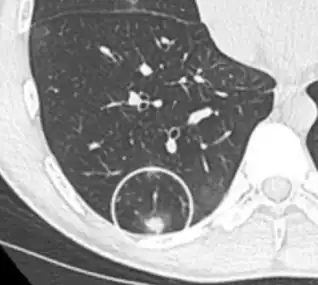

- Pleural retraction is far more common in cancers.[9] It is the pulling of visceral pleura towards the nodule.[9]

Nodule with pleural retraction.[9]

In this case, pleural retraction is seen as a triangular fat component.[9]